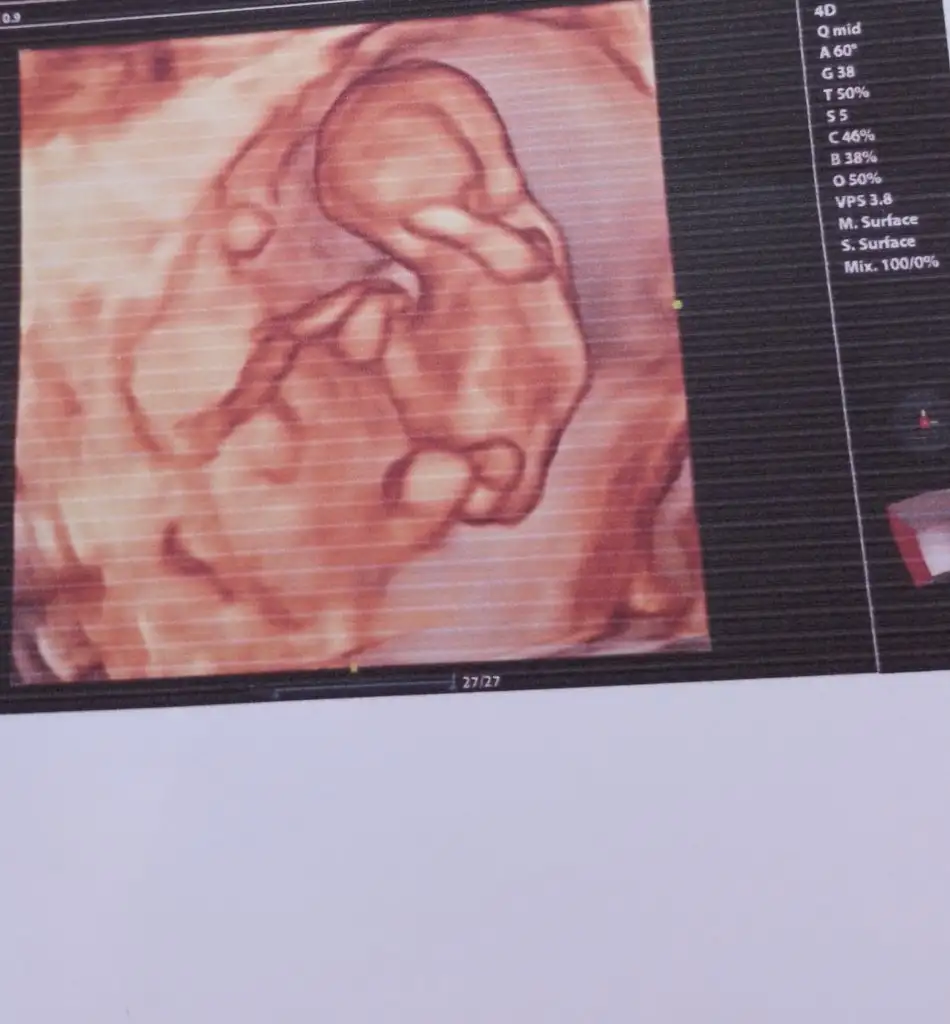

13+6 nubu kız gibi ama bacak arasında da çıkıntı var gibi sizin tahmininiz nedir